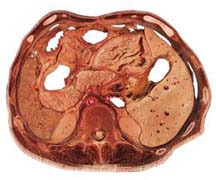

4.CT 準確性高於B超,發現率89%。對腫瘤的定位、大小範圍、與鄰近臟器的關係顯示更為直觀和清楚,增強掃描可以顯示腫瘤和周圍血管的關係腫瘤內出現脂肪密度為其特徵(圖1)。